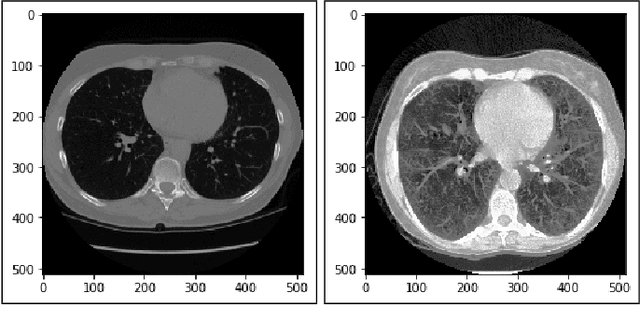

Lung cancer is one of the death threatening diseases among human beings. Early and accurate detection of lung cancer can increase the survival rate from lung cancer. Computed Tomography (CT) images are commonly used for detecting the lung cancer.Using a data set of thousands of high-resolution lung scans collected from Kaggle competition [1], we will develop algorithms that accurately determine in the lungs are cancerous or not. The proposed system promises better result than the existing systems, which would be beneficial for the radiologist for the accurate and early detection of cancer. The method has been tested on 198 slices of CT images of various stages of cancer obtained from Kaggle dataset[1] and is found satisfactory results. The accuracy of the proposed method in this dataset is 72.2%